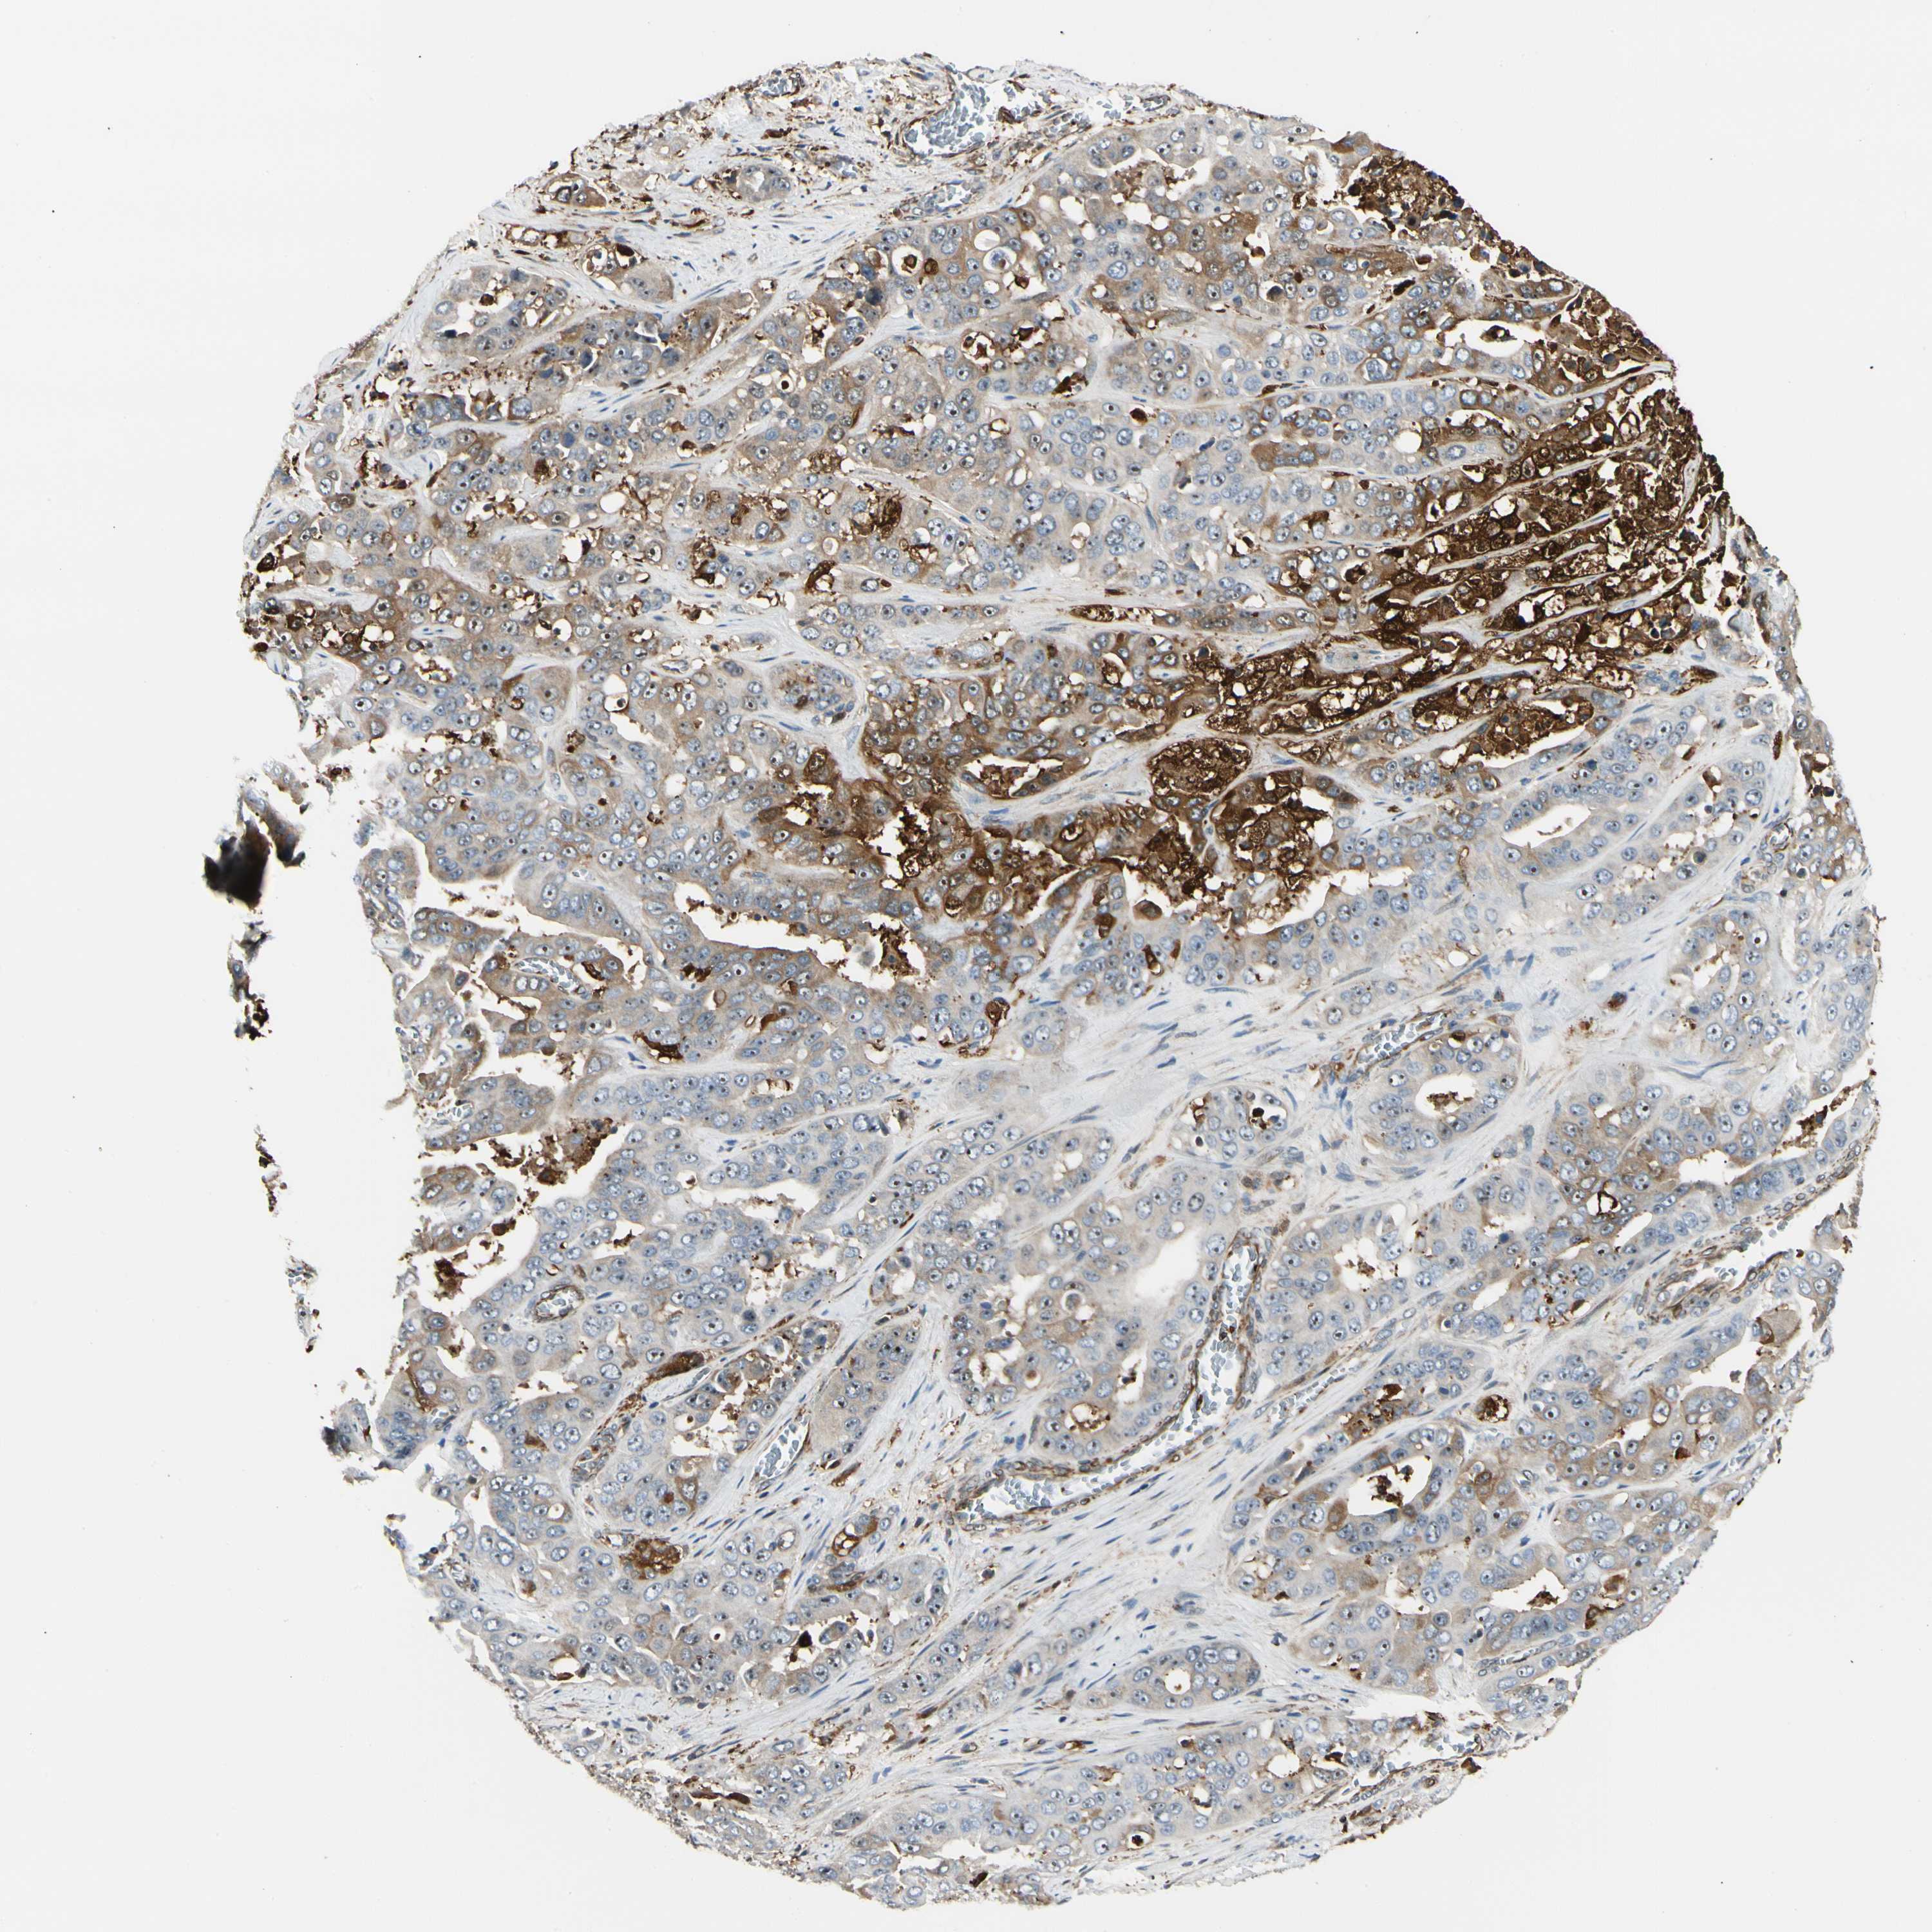

LIVER CANCER - Protein expressioni

A mouse-over function shows sample information and annotation data. Click on an image to view it in a full screen mode. Samples can be filtered based on level of antibody staining by selecting one or several of the following categories: high, medium, low and not detected. The assay and annotation is described here.

Note that samples used for immunohistochemistry by the Human Protein Atlas do not correspond to samples in the TCGA dataset.

Antibody stainingi

Antibody staining in the annotated cell types in the current human tissue is reported as not detected, low, medium, or high, based on conventional immunohistochemistry profiling in selected tissues. This score is based on the combination of the staining intensity and fraction of stained cells.

Each image is clickable and will lead to virtual microscopy that enables deeper exploration of all samples and also displays staining intensity scores, fraction scores and subcellular localization as well as patient and tissue information for each sample.

Antibody CAB008623

Staining

High

Medium

Low

Not detected

Intensity

Strong

Moderate

Weak

Negative

Quantity

>75%

75%-25%

<25%

None

Location

Nuclear

Cytoplasmic/membranous

Cytoplasmic/membranous,nuclear

Cholangiocarcinoma

Carcinoma, Hepatocellular, NOS